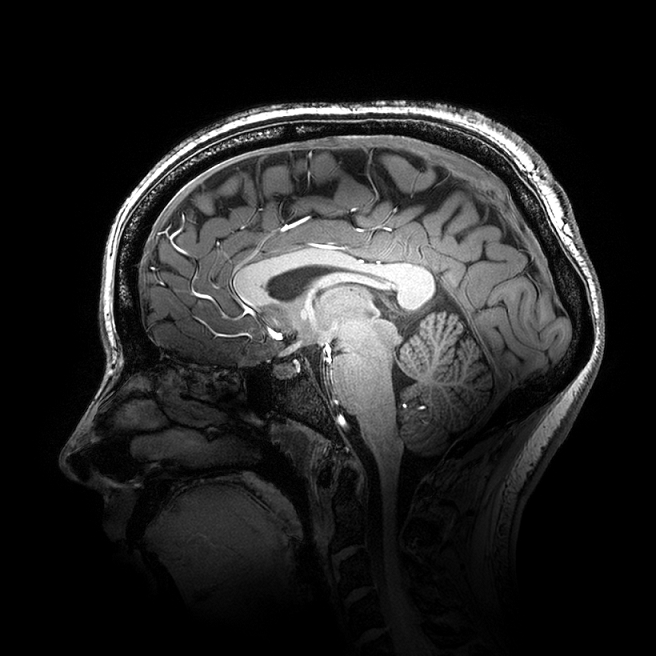

A major clinical trial has shown that by using MRI and tracking to guide the delivery of magnetic stimulation to the brains of people with severe depression, patients will see their symptoms ease for at least six months, which could vastly improve their quality of life.

The results of the trial, published in Nature Medicine, found that on average, participants showed substantial improvements in the severity of their depression, anxiety and thinking with better function and quality of life over 26 weeks with MRI neuronavigated Transcranial Magnetic Simulation (TMS). This was a substantial increase on the previous reported improvements lasting only 1-3 months.

TMS is an outpatient treatment where people have powerful magnetic pulses delivered to the left side of their head just in front of the temporal area of the scalp. The person is conscious and has 20 sessions over a four-to-six-week period. The method has been used since the 1980s to treat people with severe depression, but by targeting the precise area of the brain where stimulation is thought to be helpful, we now have evidence for a more longer lasting benefit of this treatment.

The trial, which is the first of its size in the world to look at outcomes at six months, suggest this might be achieved using functional MRI with TMS to define the exact area of the brain to hit. MRI is not normally used to deliver this treatment.

The team used neuronavigation, a computerised tracking system using light to deliver the TMS, which is a way of precisely pinpointing the area of stimulation so that the same area is targeted at all 20 treatment sessions.

Ideally when people come for a TMS session, they would sit in the exact same place, but this is rarely going to happen. This method uses light from both ear lobes and the top of the nose to measure the stimulation point from the first time a patient has the treatment. The MRI personalises the site of stimulation and then neuronavigation makes sure the same site is being stimulated at each treatment session. This reduces the variability in stimulation at each session. Since the magnetic pulse can be focused, there are usually only minor short-lasting side-effects, and the person can return to their daily activities immediately on return from the hospital.”